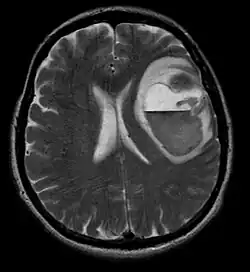

Metástases cerebrais

As metástases cerebrais são as neoplasias intracranianas mais comuns em adultos, sendo dez vezes mais comuns que os tumores cerebrais primários. Eles pisam em 20 até 40 por cento dos adultos com câncer e estão associados principalmente ao câncer de pulmão e mama e melanoma . Essas lesões resultam da disseminação de células cancerígenas pela corrente sanguínea e ocorrem mais comumente na junção da substância cinzenta e branca, onde a seção transversal dos vasos sanguíneos se altera, aprisionando embolias de células tumorais . 80 por cento das lesões ocorrem nos hemisférios cerebrais, 15 por cento no cerebelo e 5 por cento no tronco cerebral. Cerca de 80 por cento dos pacientes têm história de câncer sistêmico e 70 por cento têm múltiplas metástases cerebrais.

Avanços significativos foram feitos recentemente no diagnóstico e tratamento dessas lesões, resultando em melhora da sobrevida e controle dos sintomas. O início dos sinais e sintomas é semelhante ao de outras lesões maciças no cérebro. O método diagnóstico de escolha é a ressonância magnética com meio de contraste.

A literatura mostra resultados equivalentes para cirurgia e radiocirurgia. Este último parece ser mais conveniente, eficaz e seguro para lesões pequenas ou em regiões inacessíveis à cirurgia. A radiocirurgia é uma alternativa sensata para pacientes que não podem ser operados por razões médicas. No entanto, a cirurgia é claramente o método ideal para obter tecidos para diagnóstico e remover as lesões que causam efeito de massa. Portanto, a radiocirurgia e a cirurgia devem ser melhor consideradas como dois métodos complementares, mas diferentes a serem aplicados, dependendo da situação diferente do paciente. Por quase 50 por cento dos pacientes com uma ou duas metástases cerebrais não são candidatos à remoção cirúrgica devido à inacessibilidade das lesões, extensão da doença sistêmica ou outros fatores. Esses e outros pacientes com metástases múltiplas geralmente recebem radioterapia panencefálica como padrão de tratamento. Na verdade, chegar até quase 50 por cento deles com esta terapia uma melhora nos sintomas neurológicos e 50 até 70 por cento uma reação perceptível. A quimioterapia raramente é usada principalmente para metástases cerebrais.

Para a maioria dos pacientes com metástases cerebrais, a sobrevida média é de apenas quatro a seis meses após a radioterapia panencefálica. No entanto, pacientes com menos de 60 anos com lesões discretas e doença sistêmica controlada podem alcançar maior sobrevida porque podem tolerar uma abordagem de tratamento mais agressiva.